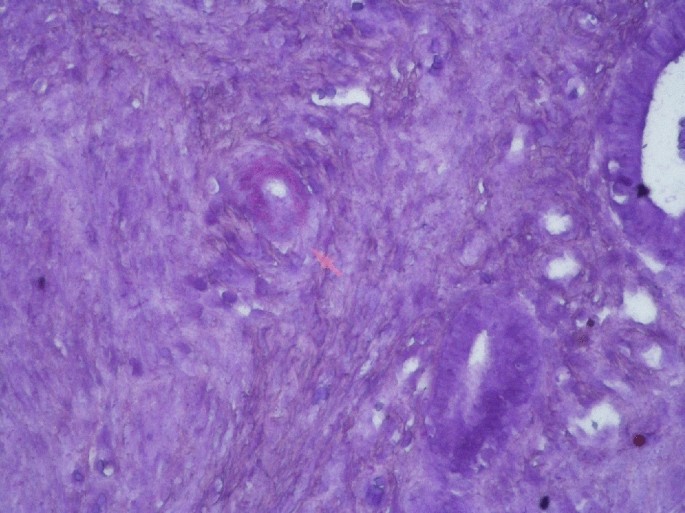

When the patient returned to our department, she had bicytopenia (anemia + thrombocytopenia, renal failure (blood urea nitrogen [BUN]: 76.3 mg/dL, creatinine [Cr]: 7.54 mg/dL) and metabolic acidosis. She underwent haemodialysis and received ES transfusion. Both protein electrophoresis and PNH panel were normal. In the PET-CT image, the spleen was extremely enlarged, and a diffuse increase was noted in gastric wall [standardized uptake value (SUVmax): 10.8]. In the endoscopic examination, diffuse hyperaemia and oedema were seen along the mucosa and walls of the gastric corpus and antrum. Samples were collected for a gastric biopsy which resulted as AA amyloidosis and chronic gastritis. Daily 2–3 units of ES transfusion were required to manage severe menometrorrhagia of the patient. In our opinion, thrombocytopenia was caused by hypersplenism, and anemia was induced by bleeding and hypersplenism. Provisional diagnoses of amyloidosis-associated massive splenomegaly and hypersplenism were made, and splenectomy was decided. Department of Gynecology initially employed hormone therapy for persistent menometrorrhagia without success. As bleeding worsened, surgery was decided. Prothrombin time, activated partial thromboplastin time, and international normalized ratio; fibrinogen, and factor VII, VIII, IX, XI, and XIII values of the patient were lying within their respective normal range, but platelet aggregation was disrupted as measured by ristocetin cofactor assay (RCof) (Factor X testing is not available in our site, therefore was not done). Thus, menometrorrhagia of the patient was attributed to platelet dysfunction and thrombocytopenia with a likely contribution of amyloidosis. The patient underwent splenectomy + hysterectomy and bilateral salpingo-oophorectomy in a single operating session. In the pathological examination, the left ovary and spleen were stained with crystal violet and Congo red which produced a staining pattern suggesting amyloids, and amyloid A staining was positive. Suspecting amyloid deposition also in the uterus, we applied uterine amyloid staining. Crystal violet staining was consistent with amyloid deposits at superficial myometrial vessel walls (Figs. 1, 2, 3). Moreover, amyloid deposits in patches were indicated at endometrial vessel walls. No postoperative complications were observed. Following the splenectomy, thrombocytopenia of the patient recovered. She was initiated on anakinra 100 mg/every other day subcutaneous for FMF-associated diffuse secondary amyloidosis. The patient had no active complaints in the postoperative 2nd month and 1.5 months after the anakinra treatment and the haemodialysis program was continued. The acute phase response and hemogram of the patient returned to normal completely. However, proteinuria was continued. (Clinical and laboratory findings of the patient are given in Table 1.)

Fig. 2

figure 2

Immunohistochemical assay tested positive for amyloid A throughout vessel walls of the spleen parenchyma (× 100)

AA amyloidogenesis may take place at various layers of the uterus. While AA amyloidosis in RA patient was detected at perivascular regions of the endometrium, the case with AL amyloidosis was shown to have deposition at myometrial blood vessels [9, 13]. Amyloids were determined in the superficial myometrium and endometrium in our case. In the AL amyloidosis case described by Copeland et al., on the other hand, a broader involvement covering uterus, cervix, corpus, fallopian tubes, and ovaries as well as the appendix and omentum was mentioned [11]. AA amyloidosis secondary to tuberculosis involving adrenal glands, liver, and kidneys in addition to ovaries which is accompanied by calcification has been described in the literature. However, it was not clarified whether the uterus was involved or not [19]. Similar to the case reported by Copeland et al., we have histopathological evidence of ovarian amyloidosis in our case.